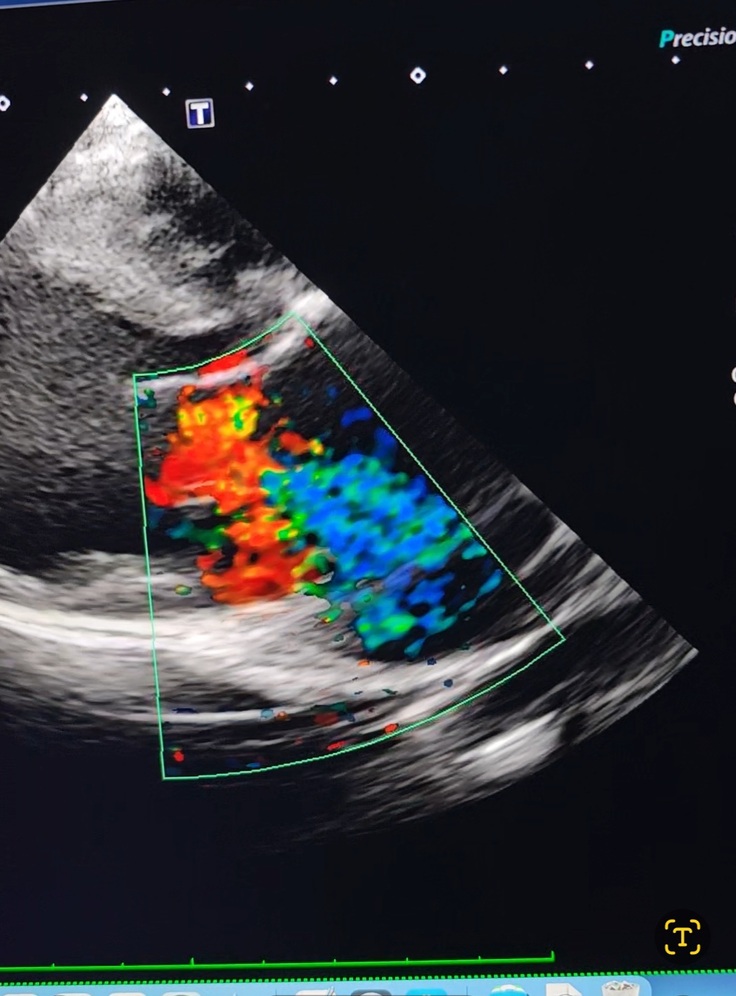

レントゲン、エコー、血液検査全て検査してやっと病名がハッキリしました。

この時既に肺にお水が少し貯まっていました。

病名は『動脈管開存症』生まれて数日で閉じるはずの血管がそのまま残っていて心臓が肥大しているのですが、ここまで大きくなった心臓は本当に数件程度だそうで、肋骨も圧迫し、気管支も背骨に押し付けられる程に大きくなっているのと肺に少し貯まっているお水を出す為に利尿剤と心臓のお薬を頂いて帰って来ました。

心臓が大きくなりすぎて僧帽弁がきっちり閉じられないので逆流のため左心房、左心室拡大。

全身に回る一番太い血管(イラスト赤い血管)と肺に繋がってる血管(イラスト紫の血管)との間にある血管が動脈管開存症という血管で閉じなければいけない血管が開いたままで繋がって、今の所は太い血管から細い血管に流れて行ってるので、心臓に負担がかかりかなり肥大してて、僧帽弁も形は綺麗なのですが、肥大しきってるせいで弁が閉じても逆流してしまうくらいに心臓が大きくなってしまってます。

↑の写真は本来動画で撮ってるのですがその動画はインスタに載せます。

Instagram @wakaba.asahiで下の方にリンク貼っています。

エコーでは縛る血管が太いらしくかなり縛る時に血管が切れる可能性が高いのも事実です。